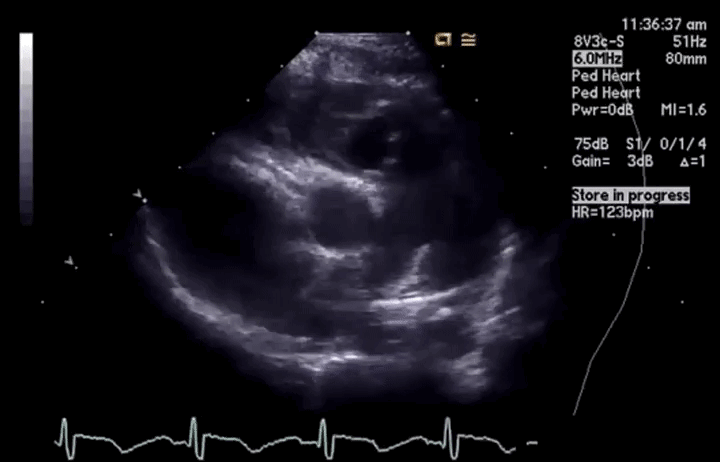

# TTE

- PLAX, PSAX, Subcostal views

左侧胸骨旁(最常用)长轴、短轴,剑突下 - PSAX, standard view for assessment of the PV

胸骨旁短轴,是 PV 评估的标准视图 - Transducer position at base of heart where PA bifurcates

- 2D Echo (anatomy and structure) 解剖与结构

- PLAX

- PSAX: level of the AV

- Thickened leaflets, doming, calcification

描述瓣叶,增厚、穹隆样改变、钙化 - Variable degree of commissural fusion

不同程度的交界区融合 - Post stenotic dilatation of MPA

狭窄后,肺动脉主干的继发扩张 - RV size is usually normal: as with RVH (>5mm) and RV hypoplasia

右室大小通常是正常的:例如伴右室肥厚 (>5 mm) 和右室发育不良

居中的是主动脉瓣,大概 1-2 点钟方向是肺动脉瓣。PV 看起来有点增厚、钙化,不像正常时的那么薄,有点穹隆样改变,活动有点僵硬,尤其是上方的瓣膜活动度欠佳。右方的肺动脉呈现瓣膜狭窄后继发的扩张(正常应该是小于主动脉部分的尺寸)。

看到这样的 2D 图像时,就应该要放上彩色血流、CW、PW 进行分析。

- Colour Flow Doppler 彩色血流

- Turbulence/aliasing 有无湍流 / 混叠现象

- Site of turbulence helps placement of Doppler cursor 湍流位置及方向有助于放置多普勒取样线,进行最大血流速度的描绘

- Associated regurgitation 伴反流

在 2D 下如果见到了肺动脉瓣增厚或穹隆样改变,可以加上彩色血流。彩色血流图可以看到湍流,在放置 CW 或者 PW 时,可以使取样线对齐湍流的方向,以获得最大速度来确定狭窄的程度

舒张期也可以观察有没有肺动脉瓣反流,若存在,也需要评估和分析